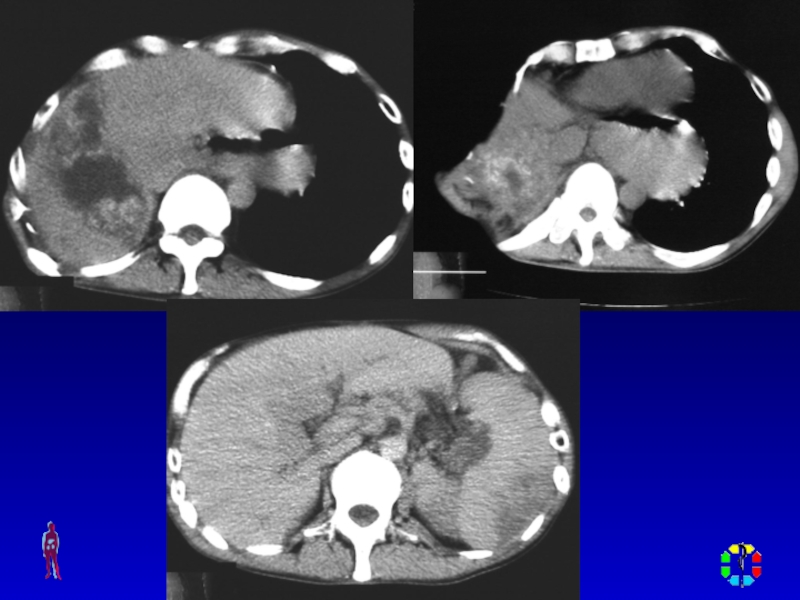

Слайд 22ДИАГНОСТИКА

Диагностическая пункция

УЗИ мягких тканей, рентгенологическое исследование , КТ,

радиоизотопное исследование.

ДИАГНОСТИКА Диагностическая пункция УЗИ мягких тканей, рентгенологическое исследование , КТ, радиоизотопное исследование.